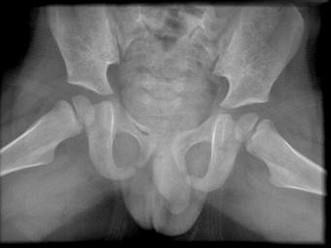

男,请根据其正常盆腔影像图像,判断其最可能的年龄 ( )A、3岁左右B、9岁左右C、12岁左右D、6岁左右E、15岁左右

问题 男,请根据其正常盆腔影像图像,判断其最可能的年龄 ( )

选项 A、3岁左右 B、9岁左右 C、12岁左右 D、6岁左右 E、15岁左右

答案 A